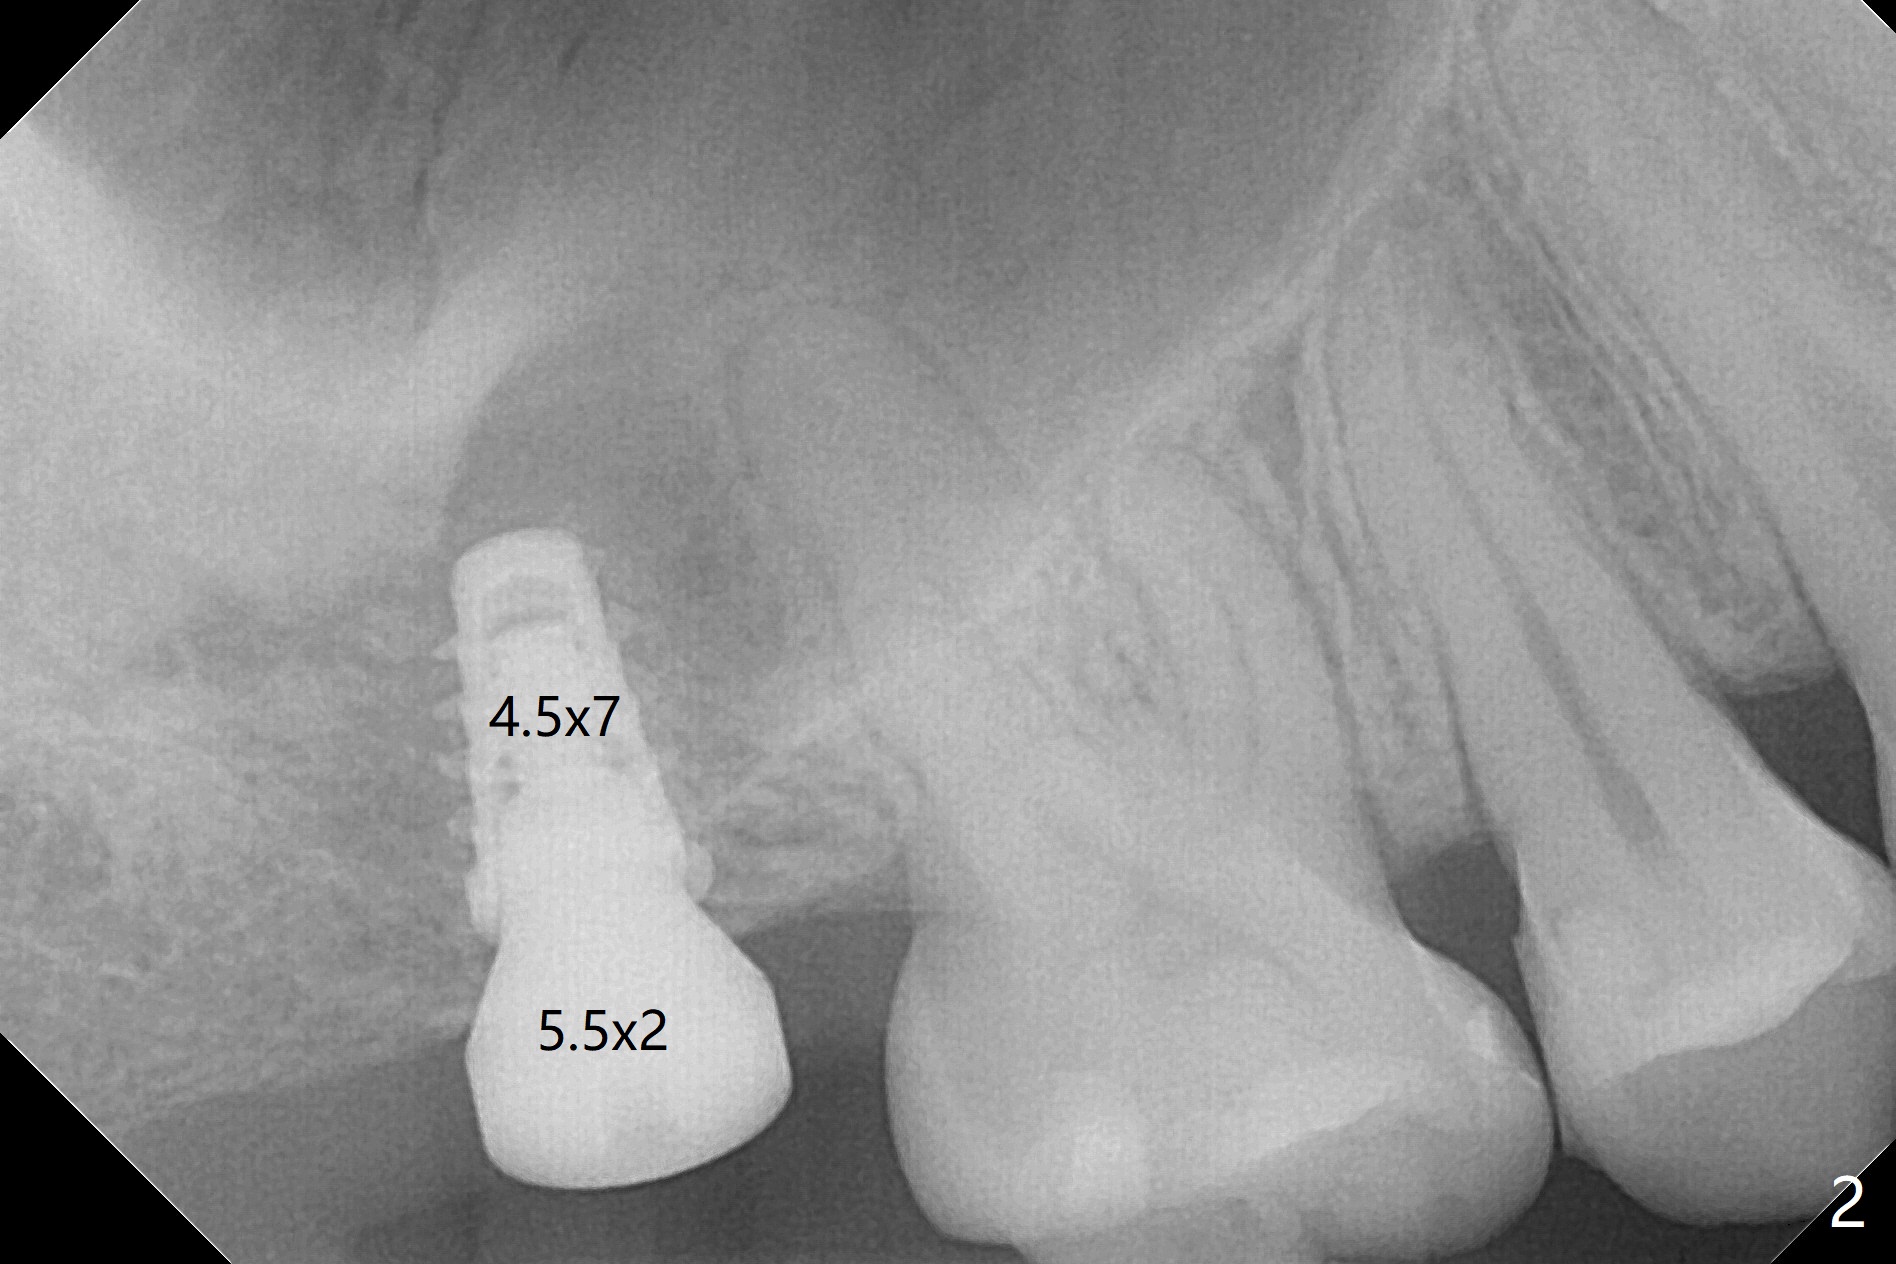

With 4-5 mm remaining bone at #2, the initial osteotomy is 4.0x3.5 mm with regular drills with sharp end. After using 3.6 mm sinus drill with round end for ~ 4 mm in depth, water lifting is conducted smoothly. After use of the same safe drill for ~ 5 mm, water lifting is done. Nose blowing indicates possible sinus membrane perforation. With insertion of collagen plug (PRF is not prepared because of thin vein), mixture of autogenous bone and allograft is lifted with 4x9 mm dummy implant with a guide (Fig.1 G). With placement of more of bone graft, a 4.5x7 mm definitive implant is placed with ~ 25 Ncm (Fig.2). Although bone graft around the implant is limited (Fig.3,4 *), the sinus membrane is lifted (in fact expanded by water) substantially (arrowheads, as compared to preop CT). The healing abutment is dislodged 1 month postop. Before impression, use sensor 1 to take PA to determine whether the abutment contacts the crestal bone or not. Take 5x5 cm CT for sinus membrane thickness. Although the bone graft surrounds the implant 3 months postop, the implant is tender when a 4.5x4(2) mm cemented abutment is being placed (Fig.5). Later a healing screw is placed (Fig.6,7). The sinus membrane has shrunk (arrowheads). Progressive loading is mandatory. The implant is uncovered with a 6x2 mm healing abutment 6.5 months postop (Fig.8). A 5.5x4(2) mm pair abutment is placed and torqued at ~20 Ncm with mild tenderness 7 months postop (Fig.9 BW). A provisional is fabricated for progressive loading because of mild crestal bone loss (*). The abutment is able to be torqued at 35 Ncm 9 months postop. Impression is taken. Return to Upper Molar Immediate Implant Trajectory II 18 Next Case with 3-4 mm Bone Screw Xin Wei, DDS, PhD, MS 1st edition 10/29/2019, last revision 02/23/2021